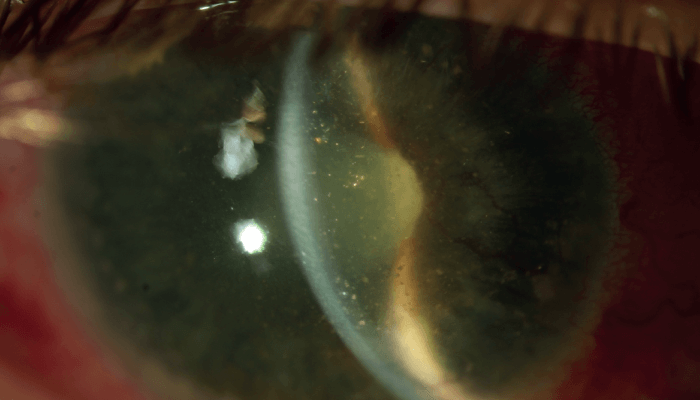

Four years later, the patient visited our department again, after suffering pain in his blind right eye for two months. His BCVA was no light perception in the right eye and 20/80 in the left eye. Slit-lamp examination of the right eye revealed conjunctival hyperemia, corneal endothelial precipitates, fibrin in a funnel-shaped anterior chamber (iris bombé), a mid-sized pupil, nonreactive to light, and a mature cataract (see Figure 1, top of the page). IOP with Goldmann applanation tonometry measured at 42 mmHg, and B-scan ultrasonography showed complete retinal detachment (see Figure 2).